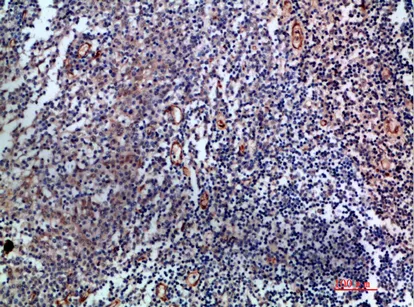

CD19 Rabbit Polyclonal Antibody

Cat: APRab08256

Size1:50μl Price1:$128

Size2:100μl Price2:$230

Size3:500μl Price3:$980

Size2:100μl Price2:$230

Size3:500μl Price3:$980